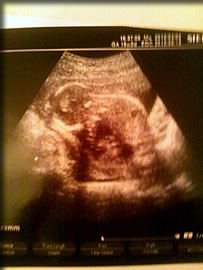

いよいよ初腹部エコー。

旦那ちゃんも診察室へ!

じゃん!

16週目のエコー

(写真のよりもっと)丸まった体勢でお出迎えてしてくれたよ。

初めは耳を手で抑えてるみたいにしてたんだけど、塞いでるわけじゃないよね?うちらの声がうるさかったかななんか可愛くて笑えちゃった。

その後ゆっくりとちっちゃな腕を下に、また上にって動かしてるのが見れたよ。

ほんと可愛い〜

背骨もくっきり見えて心音も聞けて安心した。

体重も123gで順調だって!

旦那ちゃん顔がゆるゆる♪

私もゆるゆる♪